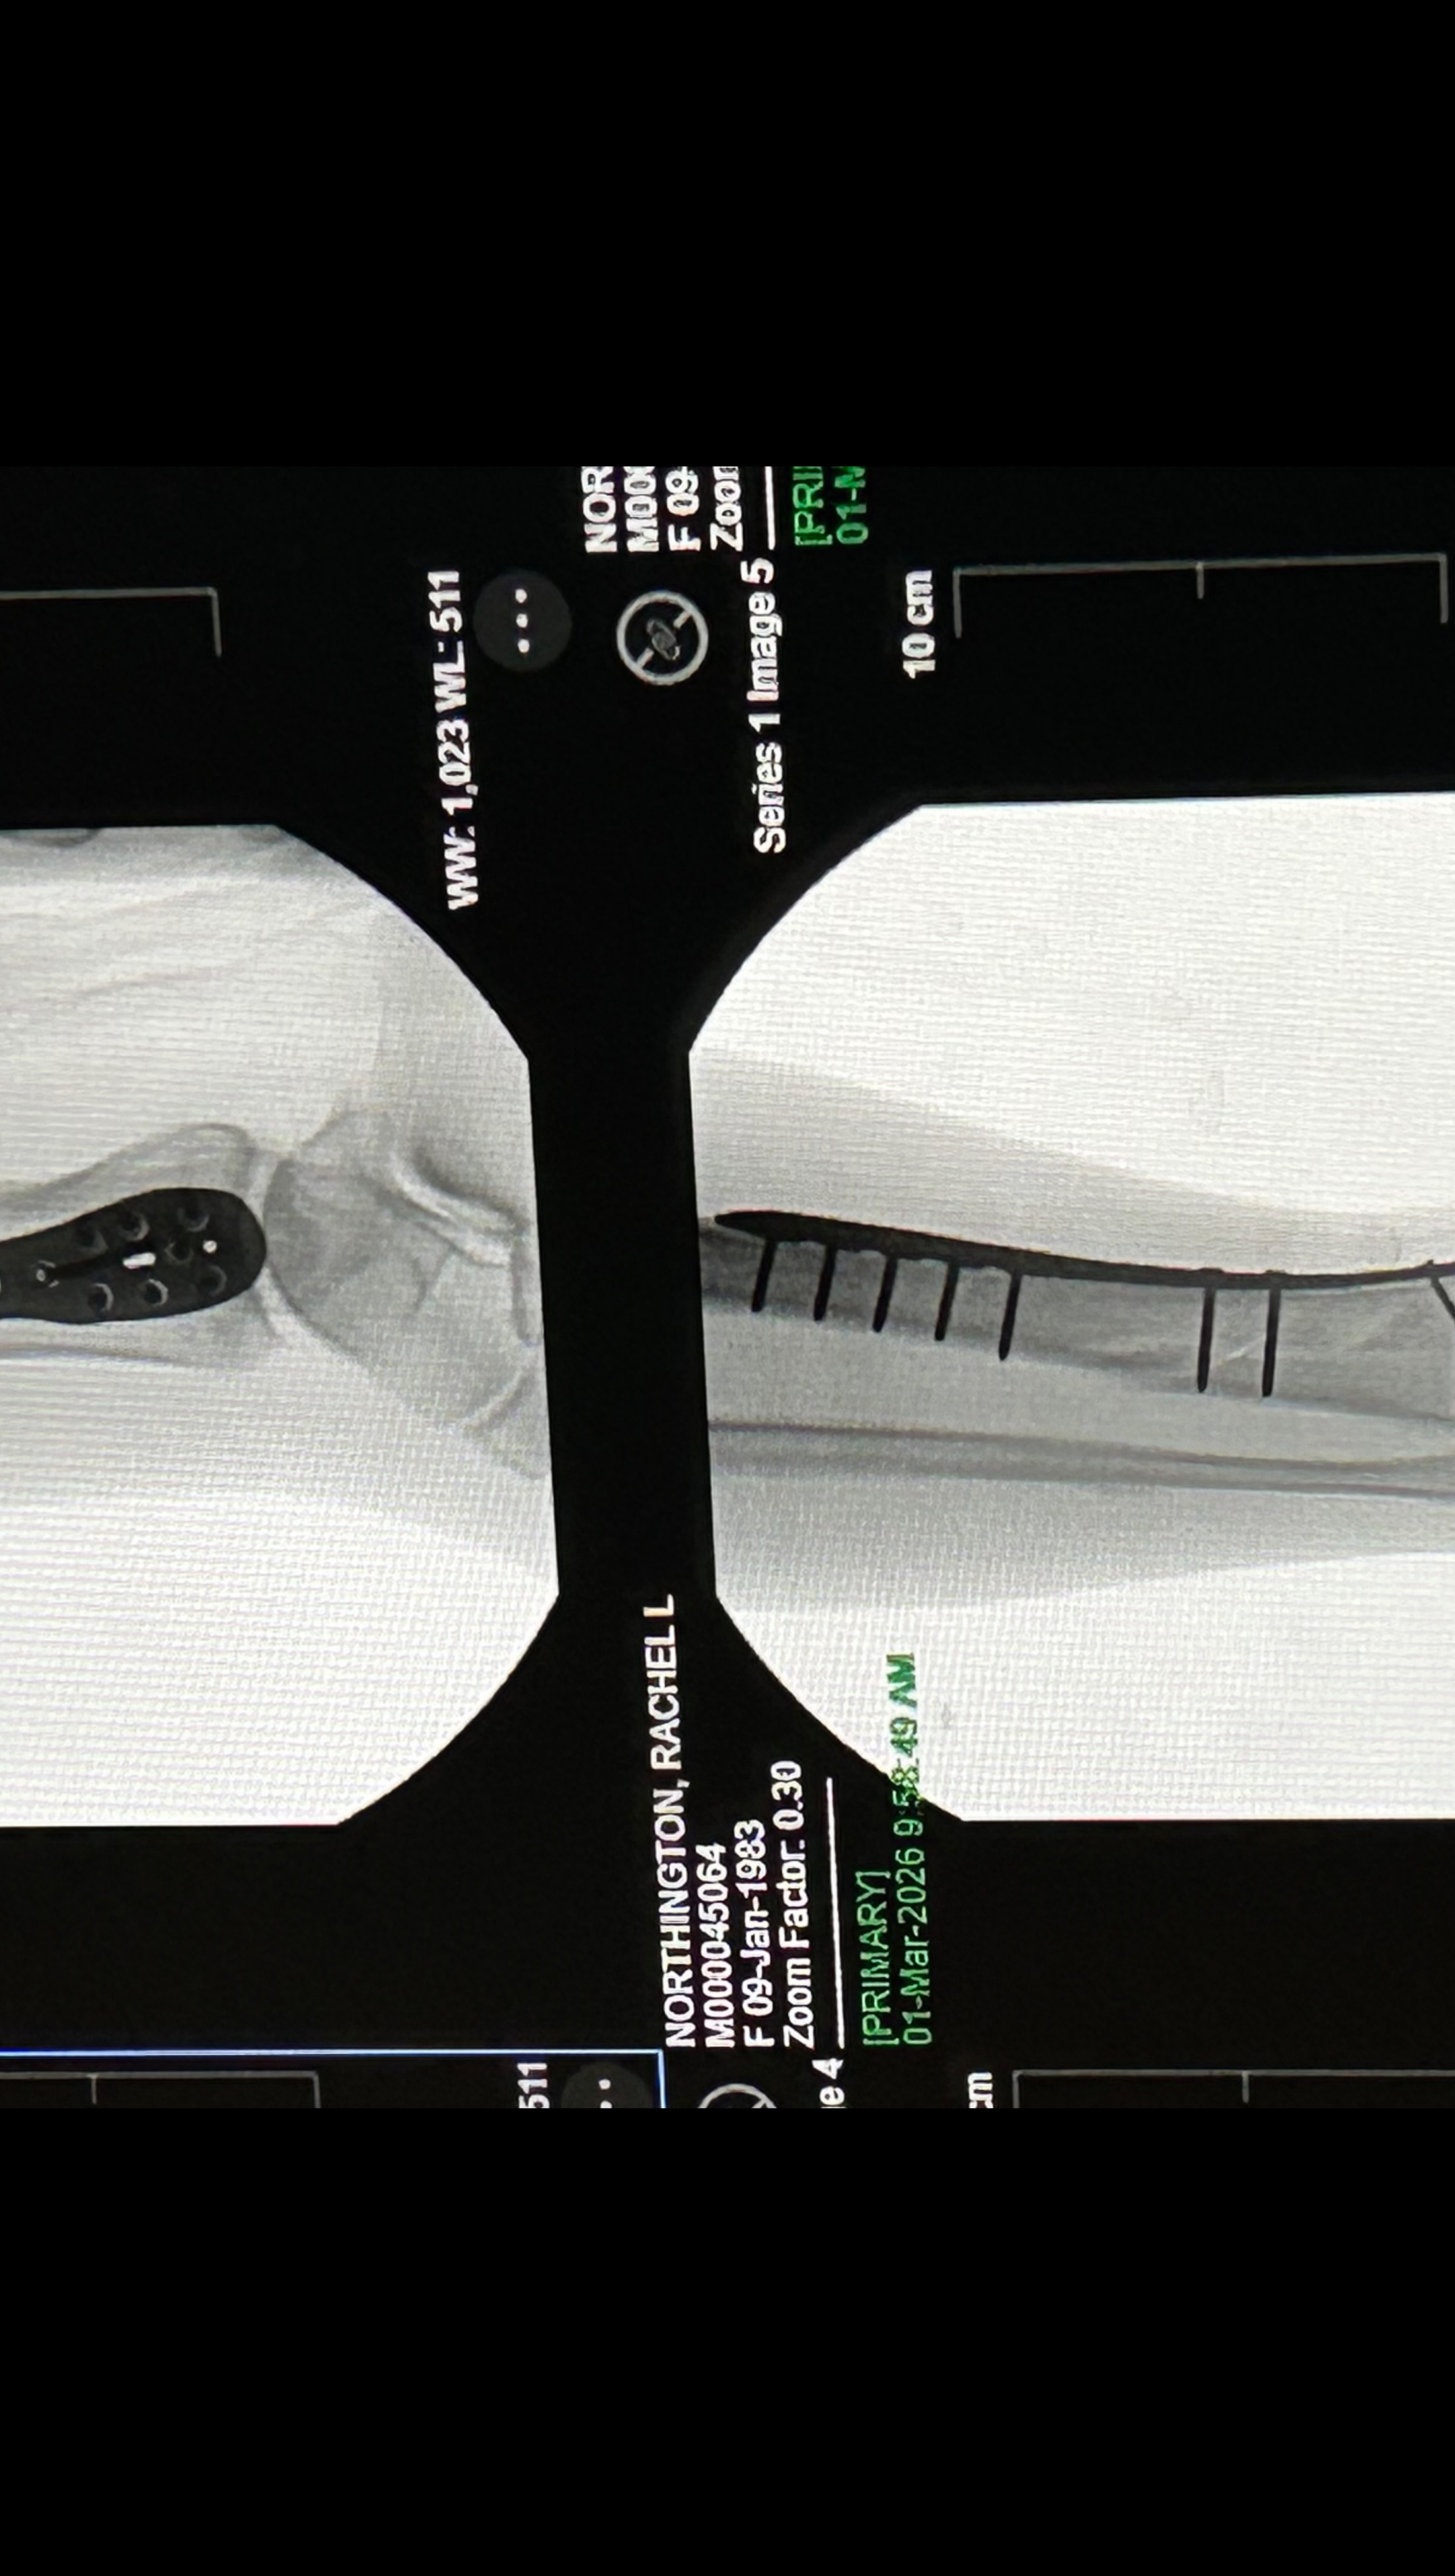

Hello my name is Rachel and I’m usually a pretty active and healthy girl. I was taken to the Murray Hospital February 15th and discharged on the 24th due to severe pancreatitis and pneumonia. I was home only a couple days and still felt very weak and tired. I attempted to go into my bathroom and somehow lost my footing and my whole body landed on my right leg and broke my right tibia and fibula (8.0 cm severely comminuted fracture of the proximal fibular shaft and 10.2 cm spiral fracture distal tibial shaft). 2 very bad fractures . It was the worst pain I’ve ever experienced! It took me 30 mins to crawl about 30 feet to my bed where my phone was to call 911 for help. The paramedics wouldn’t let me look at my leg and kept telling me to try to just lay down and relax, which was extremely hard to do. I was told my leg looked crooked and my foot was turned all the way to the side. With the help of the fire department, I was able to make it down my steps and to the ER. I had 2 doctors come in while in the ER and reset it the best they could until I could have surgery. Was supposed to be the next day but a special plate and screws had to be sent to the hospital so Sunday morning at 8am, an hour long surgery took almost 3. I now have a 9 inch place and 13 screws in my leg on one of the fractures. Depending on how the other fracture looks when I see my Ortho for follow up, I may need another surgery to put a plate on it as well. I am non weight bearing for 6-8 weeks and won’t be able to drive for no earlier than 6 months. Full recovery is a year or more. Since I am not currently working, I have applied and talked to many people about getting some sort of disability to help me keep my apartment but not getting a lot of good answers so far. I have even had my doctors send in letters stating my condition and how severe it is but it’s not getting anywhere. If anyone could find it in their heart to help me stay above water, I would greatly appreciate it!! Even a couple dollars goes a long way! All money will go to medical expenses including physical therapy, doctor appointments, medicine and the rental of medical equipment I need to get around. I didn’t want to have to make this but I’m in a rough place right now and could really use the help. Any help is appreciated. Thank you and God Bless!